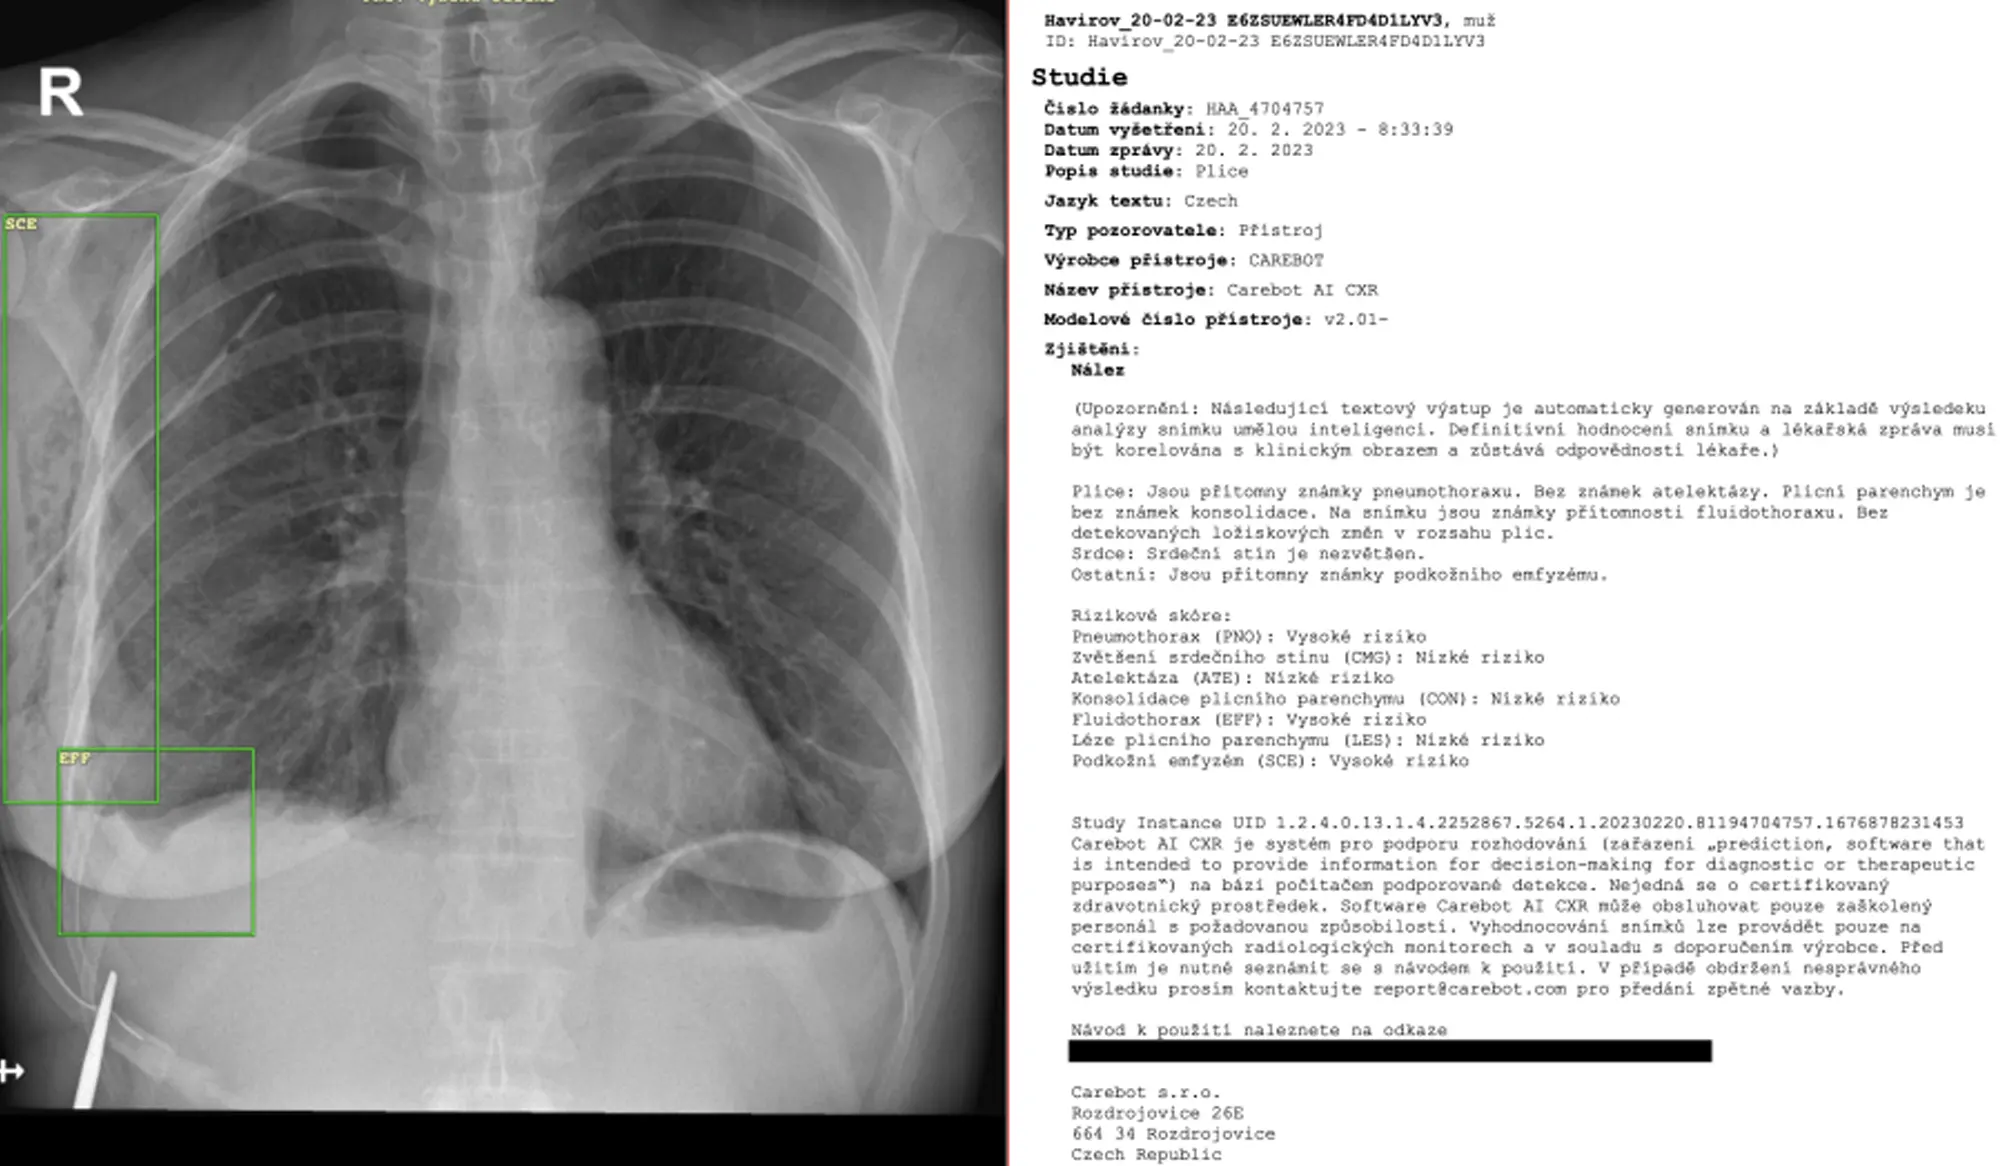

In this study, we developed a deep-learning-based automatic detection algorithm (DLAD, Carebot AI CXR) to detect and localize seven specific radiological findings (atelectasis (ATE), consolidation (CON), pleural effusion (EFF), pulmonary lesion (LES), subcutaneous emphysema (SCE), cardiomegaly (CMG), pneumothorax (PNO)) on chest X-rays (CXR). We collected 956 CXRs and compared the performance of the DLAD with that of six individual radiologists who assessed the images in a hospital setting. The proposed DLAD achieved high sensitivity (ATE 1.000 (0.624-1.000), CON 0.864 (0.671-0.956), EFF 0.953 (0.887-0.983), LES 0.905 (0.715-0.978), SCE 1.000 (0.366-1.000), CMG 0.837 (0.711-0.917), PNO 0.875 (0.538-0.986)), even when compared to the radiologists (LOWEST: ATE 0.000 (0.000-0.376), CON 0.182 (0.070-0.382), EFF 0.400 (0.302-0.506), LES 0.238 (0.103-0.448), SCE 0.000 (0.000-0.634), CMG 0.347 (0.228-0.486), PNO 0.375 (0.134-0.691), HIGHEST: ATE 1.000 (0.624-1.000), CON 0.864 (0.671-0.956), EFF 0.953 (0.887-0.983), LES 0.667 (0.456-0.830), SCE 1.000 (0.366-1.000), CMG 0.980 (0.896-0.999), PNO 0.875 (0.538-0.986)). The findings of the study demonstrate that the suggested DLAD holds potential for integration into everyday clinical practice as a decision support system, effectively mitigating the false negative rate associated with junior and intermediate radiologists.

Findings detected: 7 (atelectasis, consolidation, pleural effusion, pulmonary lesion, subcutaneous emphysema, cardiomegaly, pneumothorax)

Across all evaluated findings, AI consistently achieved high sensitivity, particularly for low-prevalence and clinically relevant abnormalities such as pulmonary lesions and pneumothorax. This significantly reduced false negatives compared to junior and intermediate radiologists. Specificity was generally lower than that of experienced radiologists, resulting in more false-positive alerts. In clinical practice, this confirms AI’s role as a safety-focused decision support tool that helps standardise detection quality and mitigates experience-related variability.